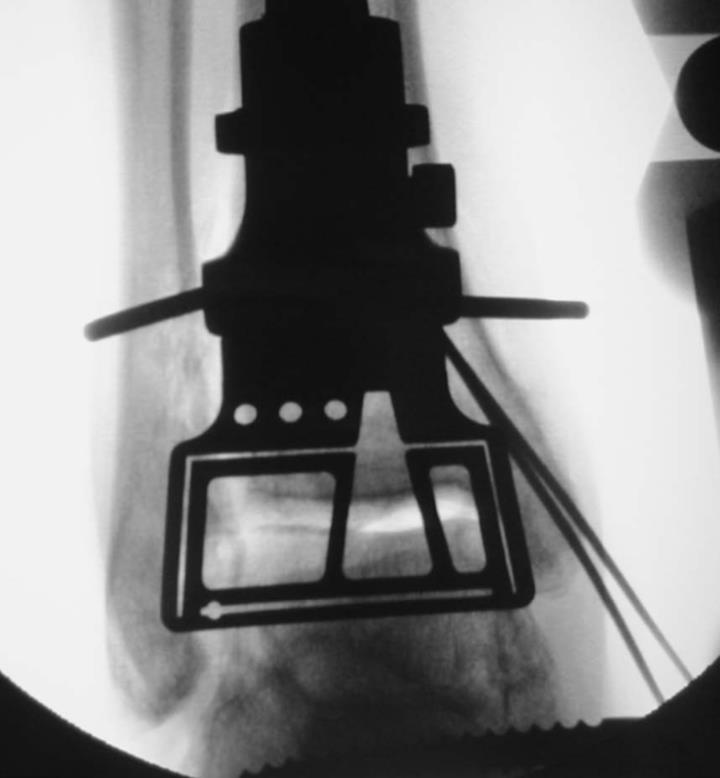

A 66-year-old man undergoes total ankle arthroplasty (TAA). An unrecognized intraoperative complication occurred and he now returns for follow-up at 6 weeks. Radiographs are shown in Figure A. Which of the following would have reduced the risk for this intraoperative complication?

This patient sustained an intraoperative medial malleolus fracture during total ankle arthroplasty (TAA). Prophylactic intraoperative pinning of the medial malleolus prior to the osteotomy helps prevent intraoperative medial malleolar fractures.

Periprosthetic fractures of the medial malleolus are more common than lateral fractures. Known risk factors for intraoperative fracture include uncontrolled saw blade excursion, excessively medial or lateral placement of the tibia prosthesis, use of an oversized tibial prosthesis, or over-distraction from an external fixator. Prophylactic K-wire (or screw) insertion through the medial malleolus prior to the osteotomy has been shown to reduce the risk of intraoperative fractures.

Figure A shows a chronic medial malleolar fracture. Illustration A shows the Manegold classification system. It is based on 3 parameters: fracture cause/timing, anatomic location and stability of implants. Illustration B shows the Manegold algorithm for treatment of TAR periprosthetic fractures. Illustration C shows prophylactic pinning of the medial malleolus prior to the osteotomy with the jig in place.